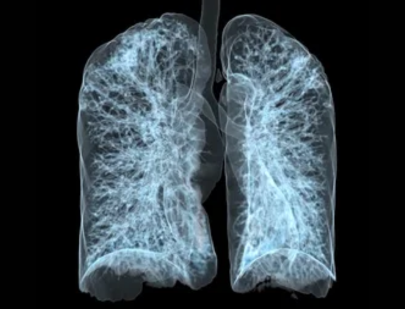

Tuberculosis (TB) is a serious infectious disease primarily affecting the lungs but can spread to other parts of the body. Caused by the bacterium Mycobacterium tuberculosis, TB is transmitted through the air when an infected person coughs or sneezes. Symptoms typically include a persistent cough, chest pain, fatigue, and night sweats. As an experienced infectious disease specialist, Dr. Ankita Baidya offers accurate diagnosis and treatment for TB. Early detection and treatment are critical in preventing complications and the spread of TB to others. Dr. Baidya ensures that every patient receives comprehensive care tailored to their needs.